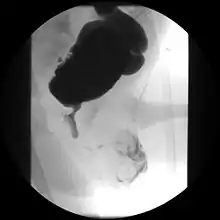

Cystourethrograph showing bladder obstruction with dilation of urethra and bladder

Ultrasound imaging can give information on the shape of the bladder, post-void residual volume, and evidence of kidney damage such as kidney size, thickness or ureteral dilation.[8] Trabeculated bladder on ultrasound indicates high risk of developing urinary tract abnormalities such as hydronephrosis and stones.[9] A voiding cystourethrography study uses contrast dye to obtain images of the bladder both when it is full and after urination which can show changes in bladder shape consistent with neurogenic bladder.[8]